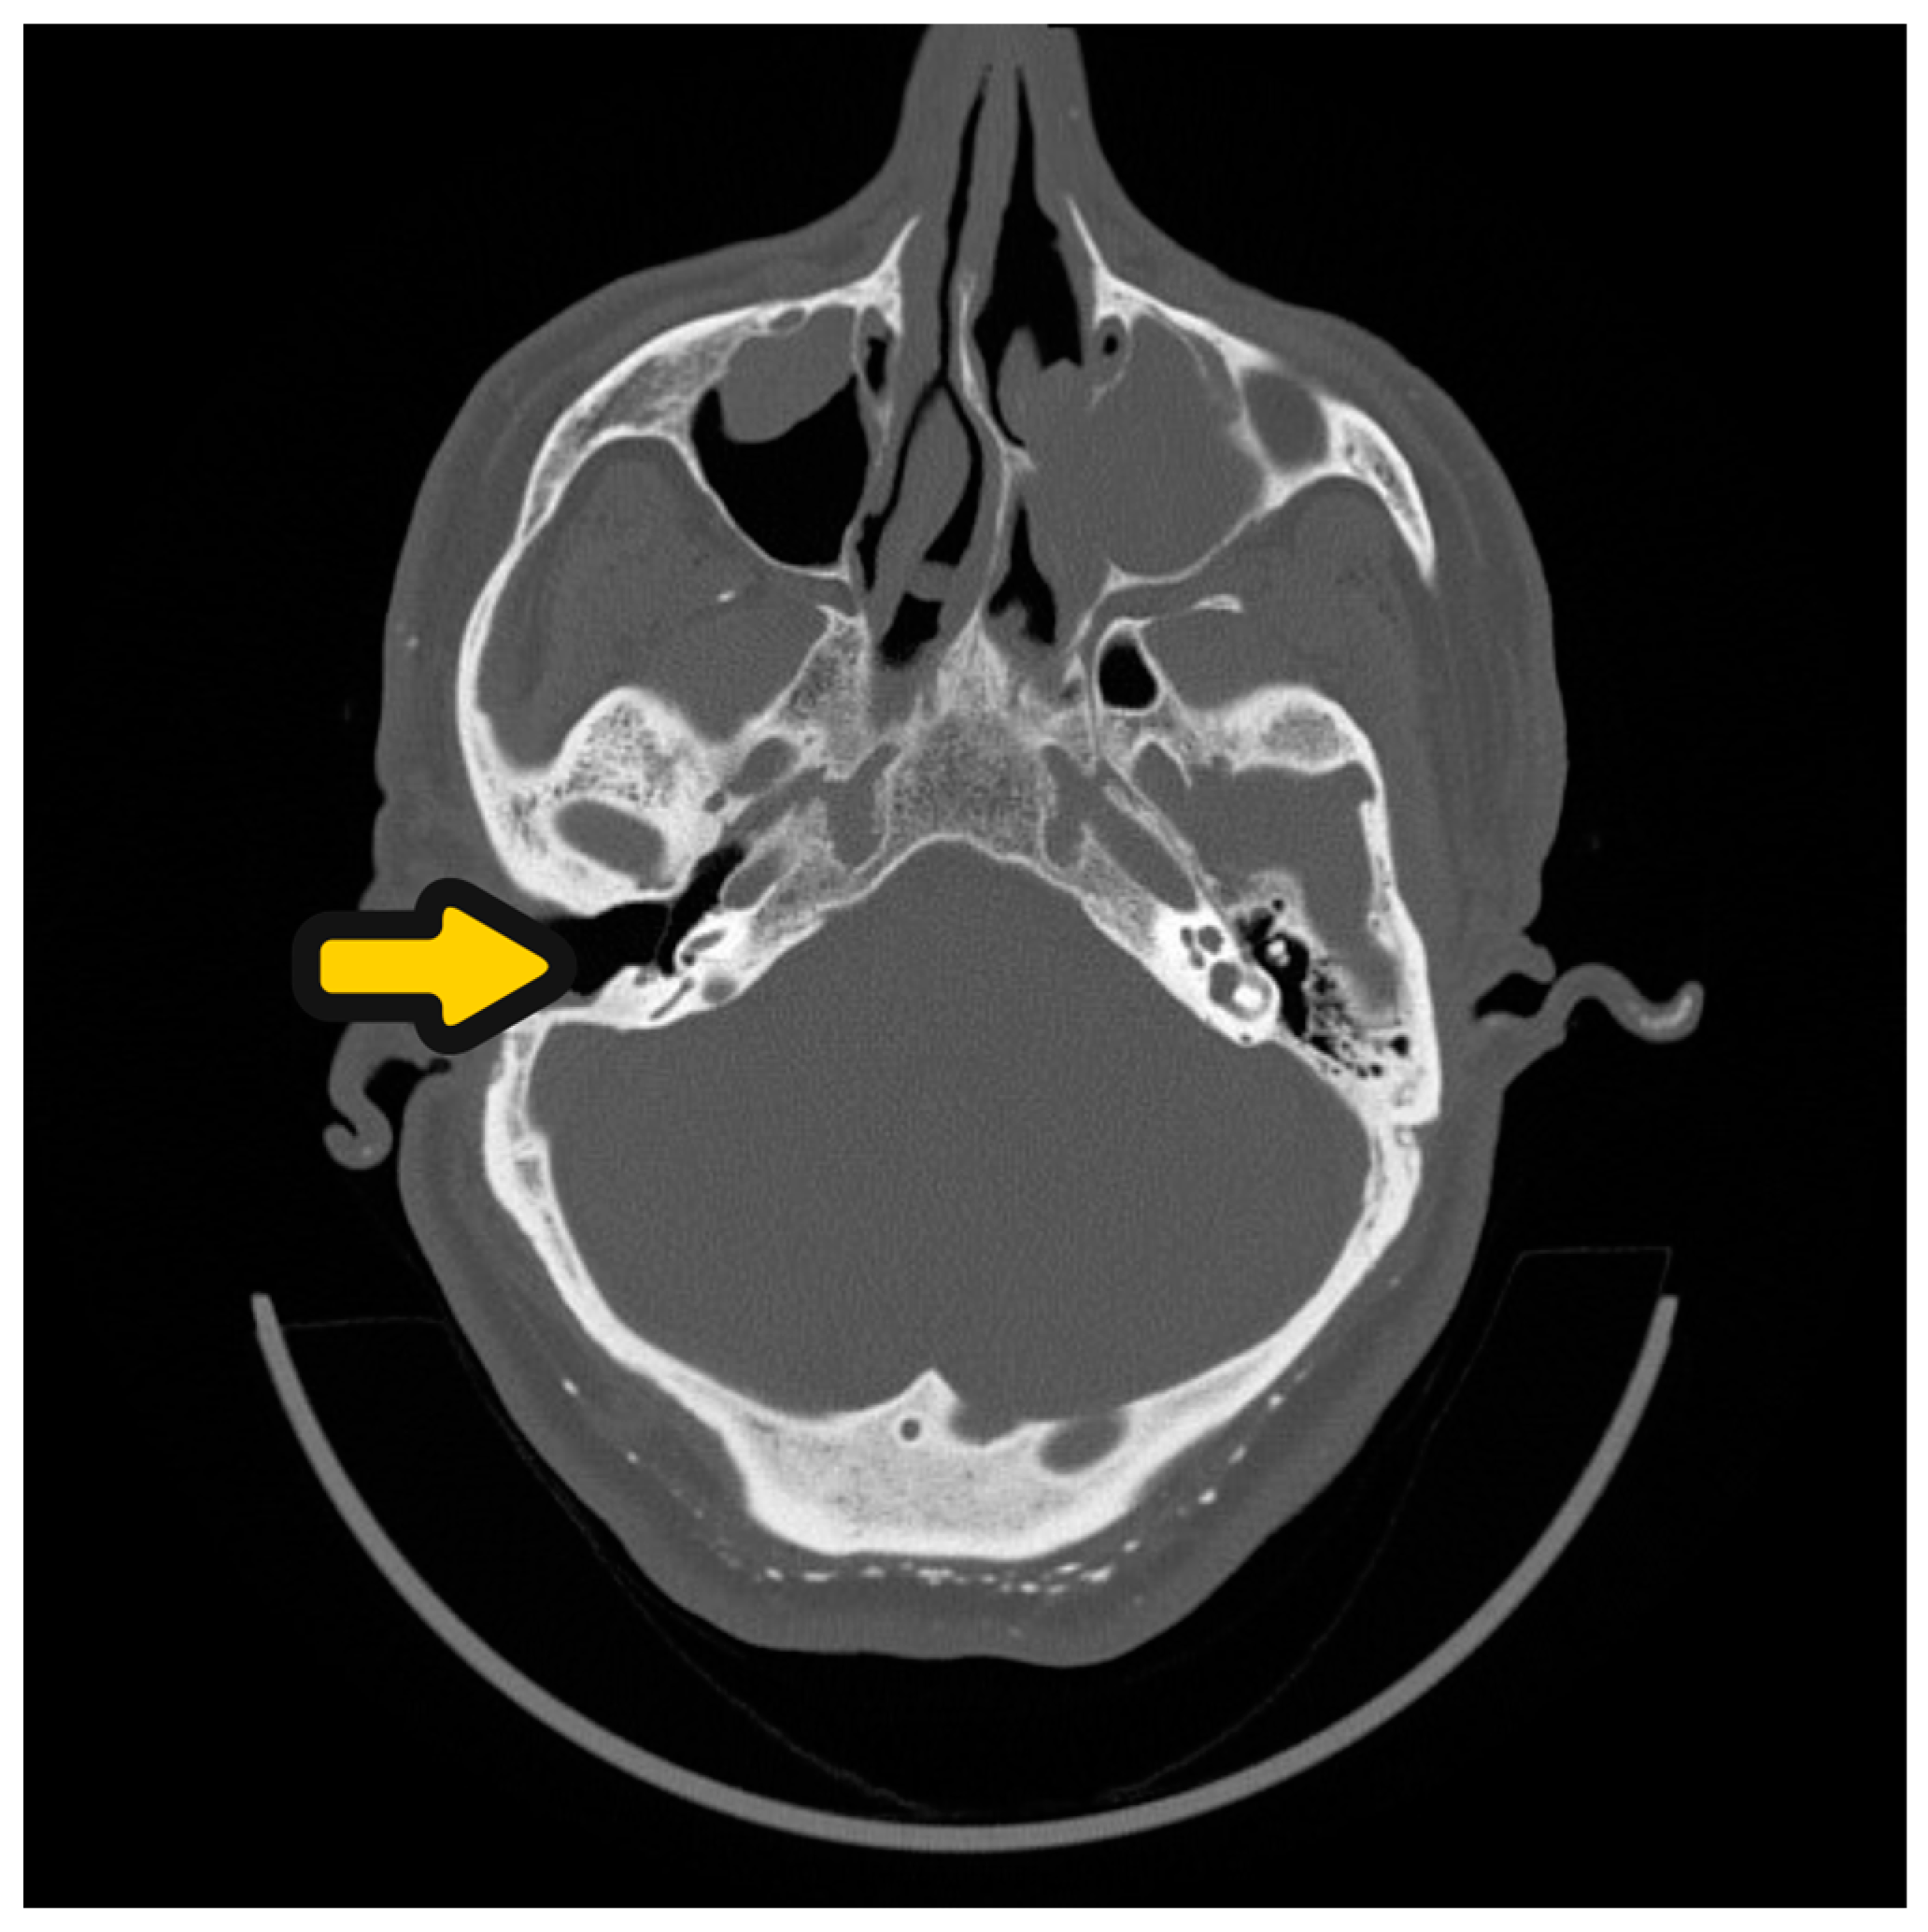

Figure 5.

HRCT of the ear before SP and CI procedure. Open right-ear cavity after first ear surgery—yellow arrow.